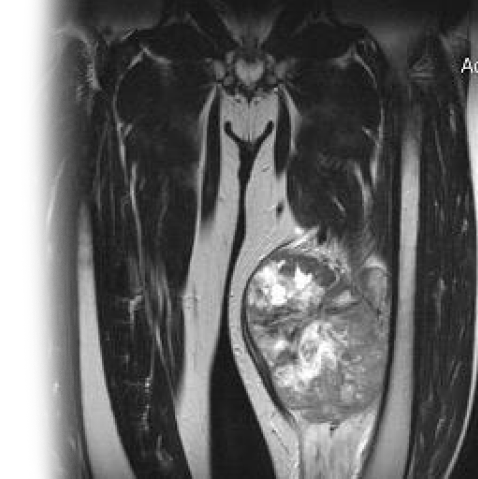

Магнитно-резонансная томография мягких тканей с контрастированием – важный метод исследования с введением контраста, которое позволяет визуализировать мышцы, связки, сухожилия, подкожно-жировую клетчатку.

Также проводится МРТ мягких тканей одного сегмента конечностей с контрастированием.